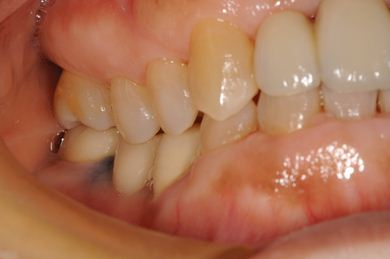

抜歯即日スピードインプラント治療

| 性別/年齢 | 女性 / 52歳 | ||||||||||||||||||||||||||||||||

| 主訴 | 歯周病で歯の位置がずれてしまった。 | ||||||||||||||||||||||||||||||||

| 治療内容 | インプラント2本(抜歯即日スピードインプラント)、メタルボンドセラミッククラウン4本 | ||||||||||||||||||||||||||||||||

| 総治療費 | 1,269,450円 | ||||||||||||||||||||||||||||||||

| 治療期間 | 10ヶ月 |